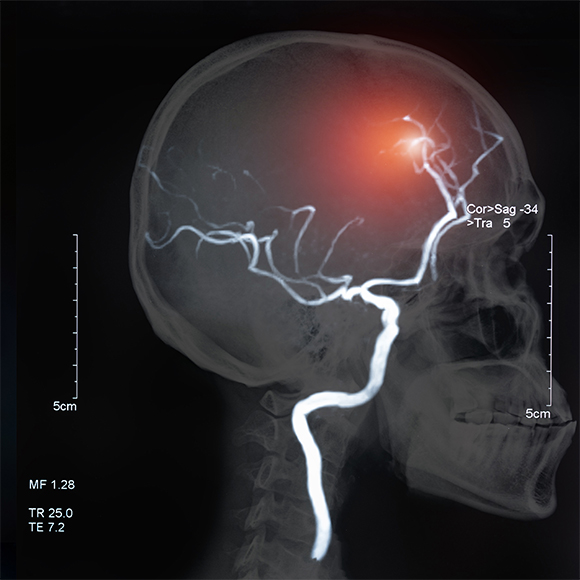

كيف يمكن التّمييز بين العوامل الجسديّة والنّفسيّة، عند قياس الألم في الدّماغ؟ كما ذكرنا سابقًا، خضع المشاركون في الدّراسة للألم عندما تمّ وضع أيديهم في ماء بدرجة حرارة مرتفعة. في الوقت نفسه، تمّ فحصهم بواسطة التّصوير المقطعيّ بالإصدار البوزيترونيّ (Positron emission tomography أو باختصار PET)، والّذي يستخدم لفحص العمليات الأيضيّة في جسم الإنسان. تبيّن أنّه عندما سمع المشاركون عبارات مهدِّئة أثناء التّحفيز المؤلم، كان هناك نشاط أقلّ في مناطق الدّماغ المرتبطة بالشّعور بالألم، مقارنة بالمشاركين الّذين لم يتمّ التّحدّث إليهم بطريقة مهدّئة، وذلك على الرّغم من أنّ جميعهم قد تعرّضوا لنفس درجة حرارة الماء. أي أنّ التّجربة الحسّيّة للألم في الدّماغ تتأثّر بعوامل إضافيّة، وليس فقط بمحفّز الألم وحده.

عندما سمع المشاركون في البحث عبارات مهدئة أثناء الخضوع للتّحفيز المؤلم، كان هناك نشاط أقلّ في مناطق الدّماغ المرتبطة بالإحساس بالألم. صورة لفحص PET توضّح نشاط الدّماغ أثناء التّحفيز المؤلّم | Montreal Neurological Institute / Science Photo Library